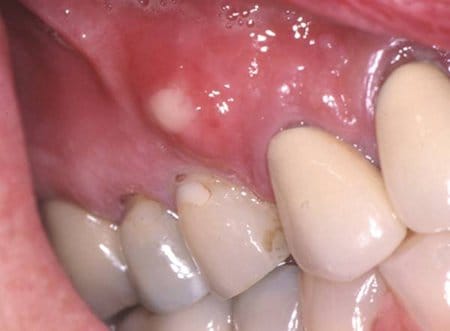

Tengo una herida en la encía, ¿Qué podría ser?

Tengo un pedacito de la encía levantada (circulo) y dura sobre el colmillo izquierdo, desconozco si me cepille muy fuerte, queme o algo por el estilo, ¿Qué podría ser? No duele nada! Y es muy pequeña.